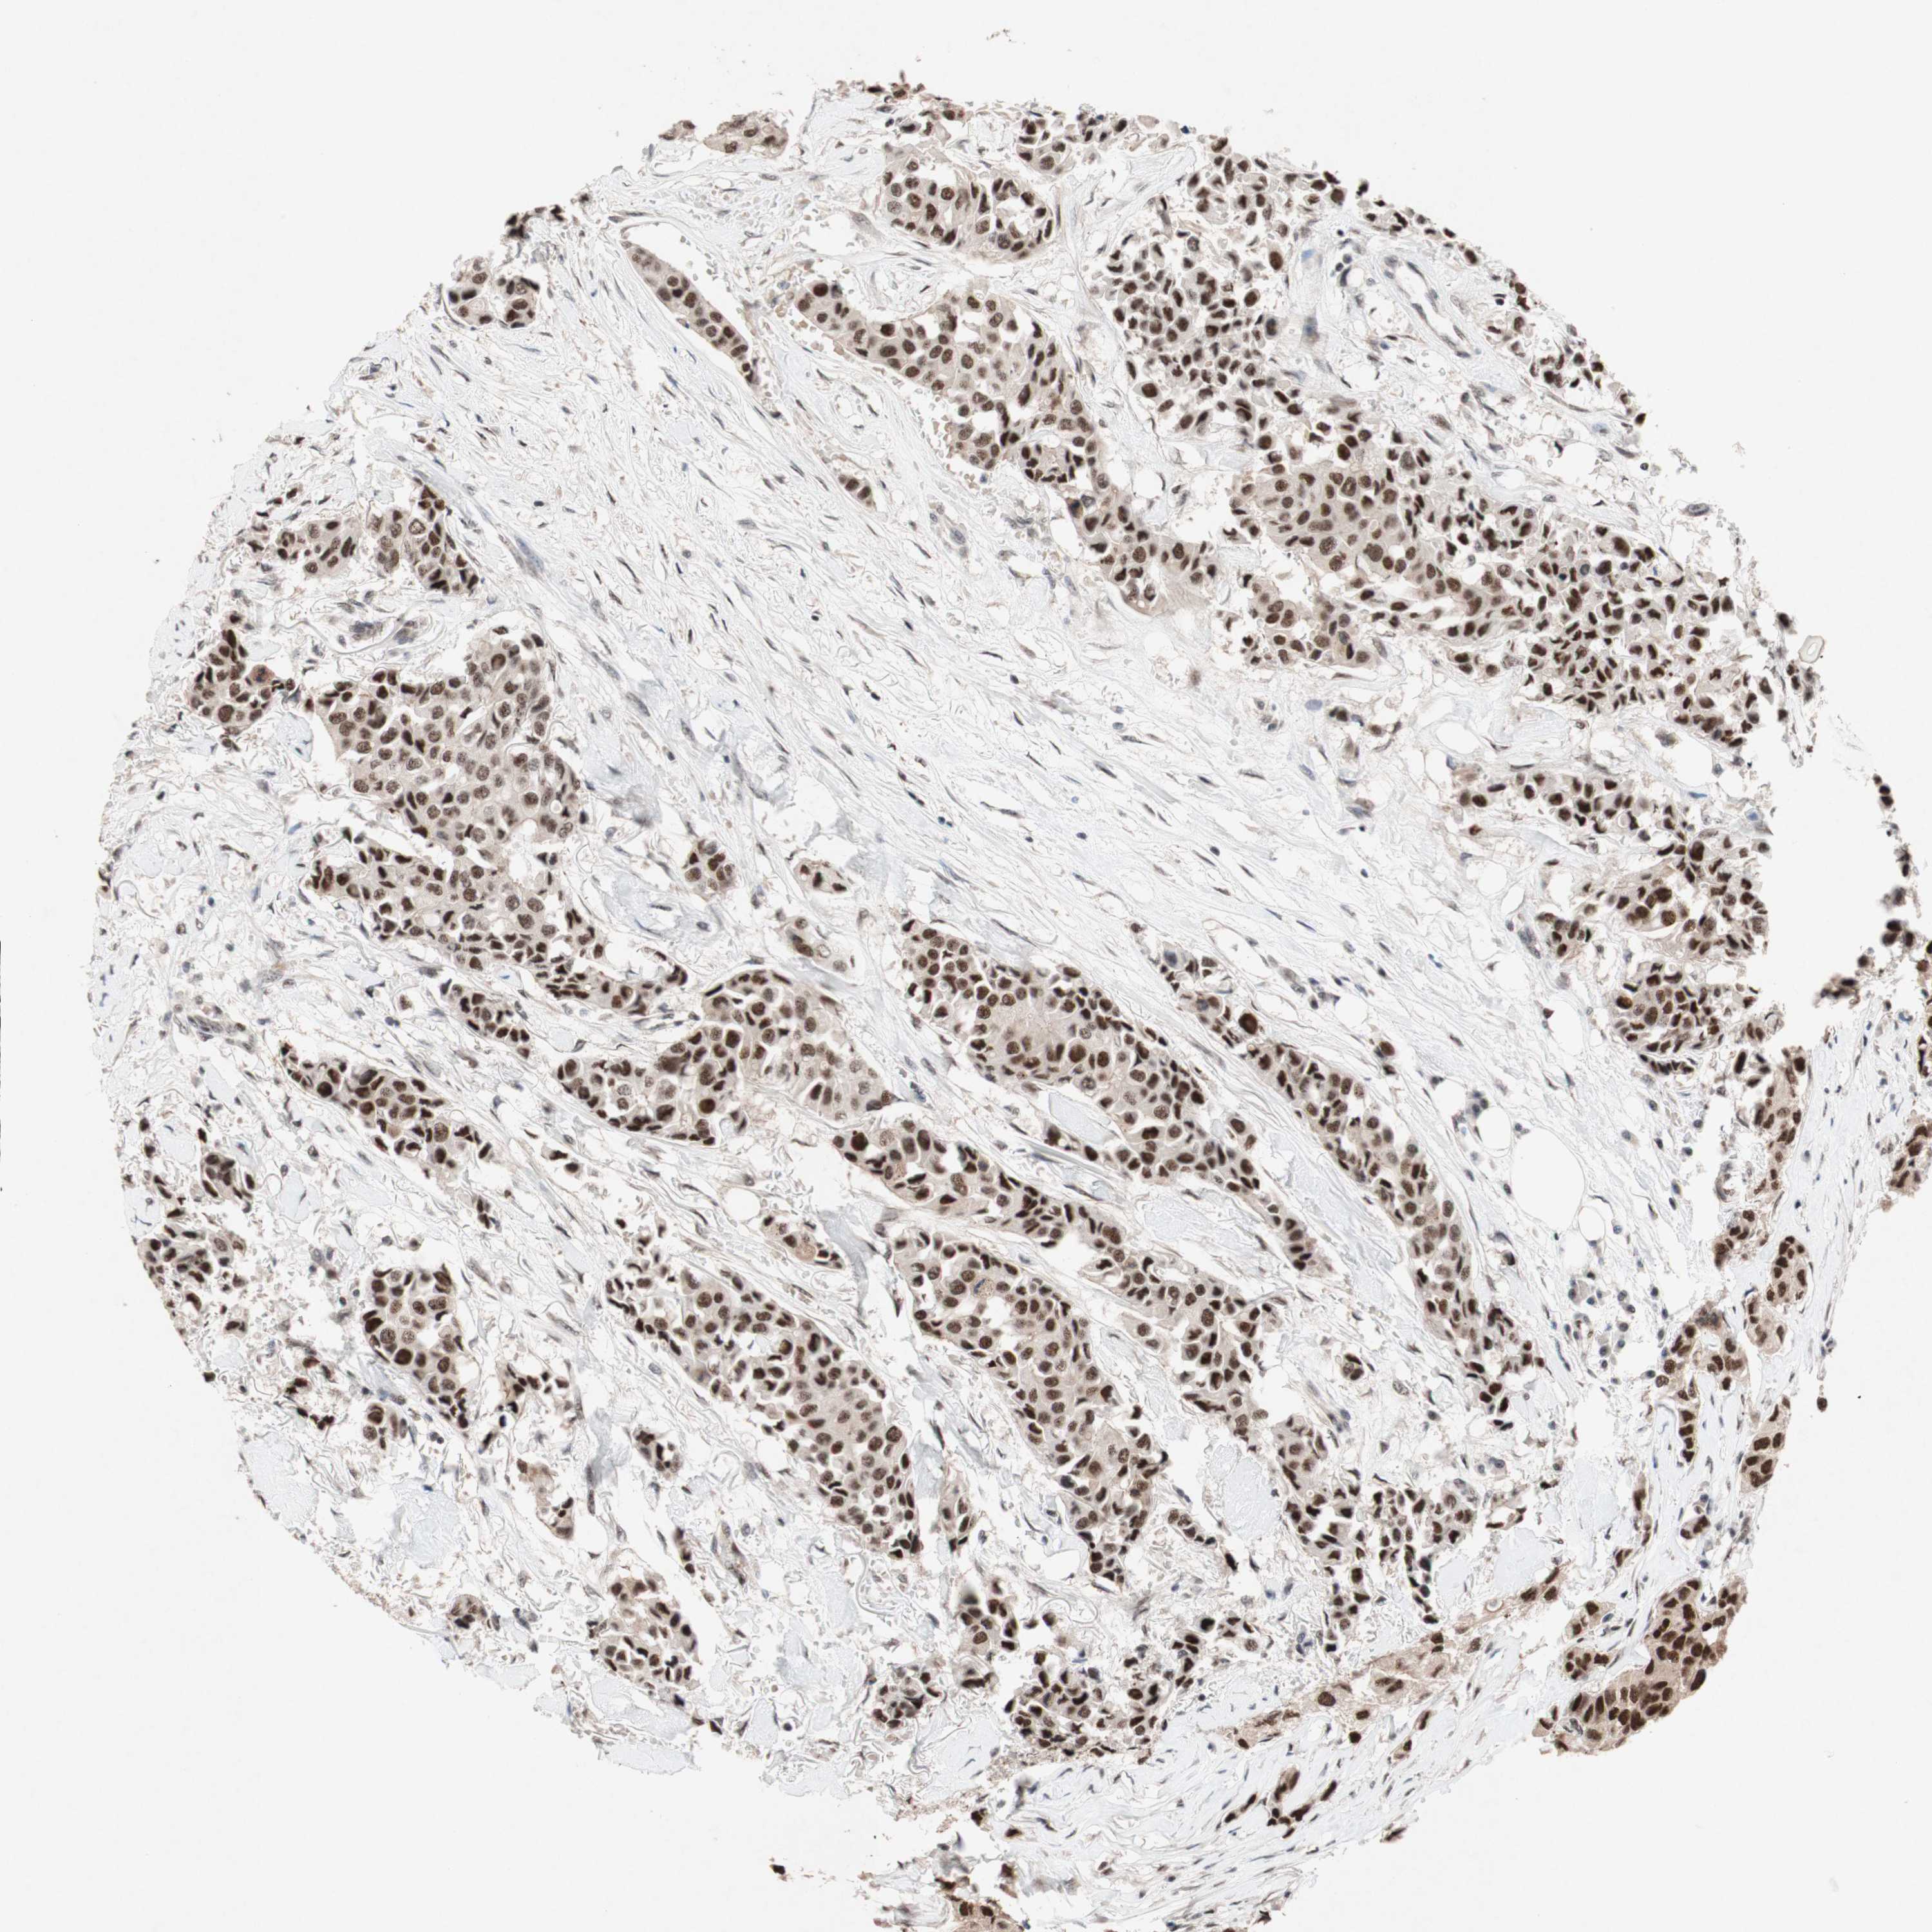

TLE1

CANCER BREAST CANCER Show tissue menu

BRCA TCGA BRCA VALIDATION PROTEIN EXPRESSION